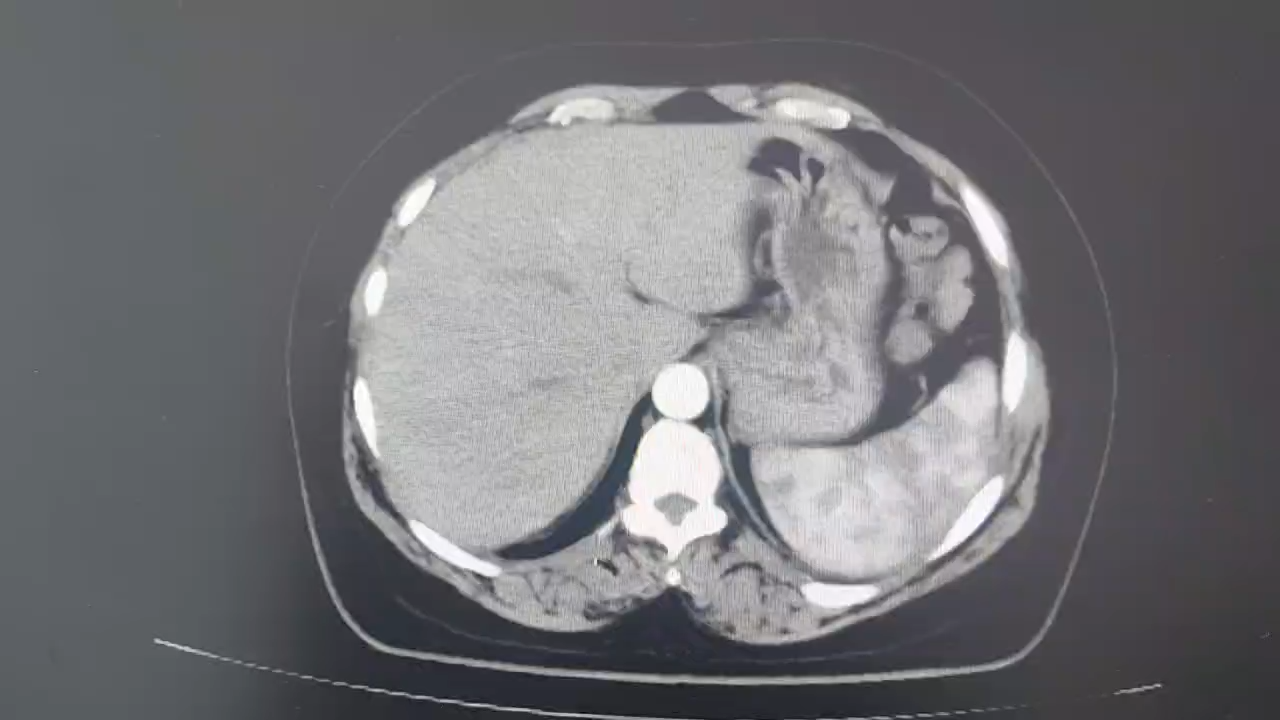

西地兰vip普外科医师

文/西地兰 特别声明:所有观点仅代表个人言论 特别声明:与当事双方均无利益相关 山东男孩,目前全网沸沸扬扬,看过一些观点,直言不讳地说,大多偏颇。要么一股脑地指责医方的全责,甚至有说千万别在县医院看病。要么又为医方无休止的遮羞,认为这样的手术在县医院做下来已经非常了不起。而我想到的是,以后面临类似的病例,我们怎么办?那么我们不如来一次专业的病案讨论。既然是事后讨论,难免有事后诸葛亮的感觉,但是假如下一次,同行们遭遇这样的病例,如何处置?这是医疗行业所面临的问题。希望我整理的这些思路和相关病例,对同行们有所帮助!就目前的资讯外界不足以判断是否需要急诊,如果需要急诊,那么只能根据术中所见进行处理,

目前知道的消息,第一,术前发现一个血肿,然后做增强CT发现一个占位,没说血肿与肿瘤的关系,术后病理没有描述肿瘤出现破裂出血,大概率就一个小血肿,我就不明白当地主任凭哪个指针去给这小孩开急诊刀的?哪个指南告诉他需要急诊开?第二,诊断不明确他想的不是进一步检查,一边观察一边进一步查,他反而选择腹腔镜探查,这个探查的指针在哪?第三,腹腔一个血肿,没有活动性出血,没有血压心率出现问题,为什么要开腹进去碰它?不能等血肿吸收再明确肿瘤性质吗?第四,1点进腹,3点病理结果出来,按这个时间还算顺利,应该还没出事,孩子还算平稳,病理是低度恶性,切了就治愈,他一年能开几台这手术,就敢继续做,拿孩子练手。第五,后面

2023年10月26日,来自山东菏泽市成武县的小烨和他家人的命运被彻底改变了。这个原本阳光、可爱的小男孩在一次意外被撞击后,在医院检查出了腹腔内存在肿瘤,并在手术中被切除了包括十二指肠、胰腺、大部分胃和小肠等多个器官。此后便无法再像正常人一样吃饭、喝水,活着要靠长期静脉注射营养液。一份2024年12月由第三方机构出具的司法鉴定意见书显示,当时给小烨做手术的成武县人民医院在该医疗行为中存在过错,与小烨的损害后果之间存在因果关系,建议医疗过错在损害后果中的原因力大小为同等原因。此外,另一份由成武县卫生健康局在2025年9月28日发出的书面答复中显示,成武县人民医院存在24小时内未完成病历;手术知情